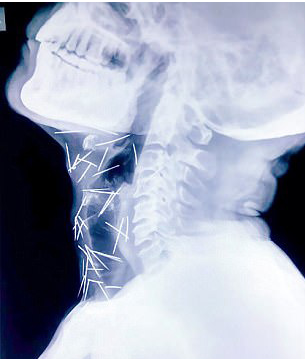

米纳在当地的一家铁路公司工作,他的家人也对事件毫不知情,迄今为止,他们问诊的所有医院中没有一间愿意做手术把针取出,75根针中有40支根于喉咙、25根在右腿、2根在手臂。米纳被迫只能在孟买的病床上等待。

米纳的儿子表示,他的父亲因感到疼痛所以到医院进行脚部手术,检查后才发现原来疼痛来自于这些针。他说:“我们看到X光照片后感到非常害怕,我问过父亲数次,他都表示没有相关记忆。”